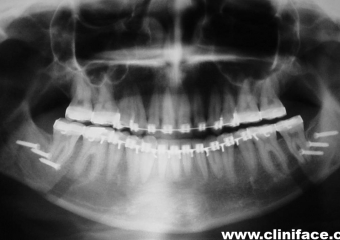

Raio x panorâmico inicial

Raio x panorâmico final